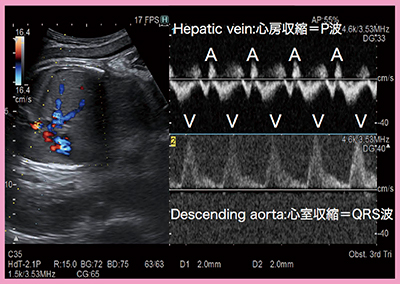

1)胎児不整脈診断

多くの医療機関では,超音波のMモード法やPW法にて上大静脈–上行大動脈同時血流波形(SVC-aAo)法や,肝静脈–下行大動脈同時血流波形(HV-DAo)法1)を用いて胎児不整脈の診断を試みている。しかし,SVC-aAo法は断面の描出に熟練を要するほか,胎位の影響を受けやすい,ドプラ波形の重なりにより開始点の判読が難しい場合がある,などの課題がある。一方,HV-DAo法は,Dual Gate Dopplerを用いることで,SVC-aAo法と同様の不整脈の鑑別診断をより簡便に行うことができる(図3)。図のように描出が薄い波形でも,Dual Gate Dopplerでは重なりがないため計測しやすいというメリットがある。

図3 Dual Gate DopplerによるHV-DAo法での不整脈診断